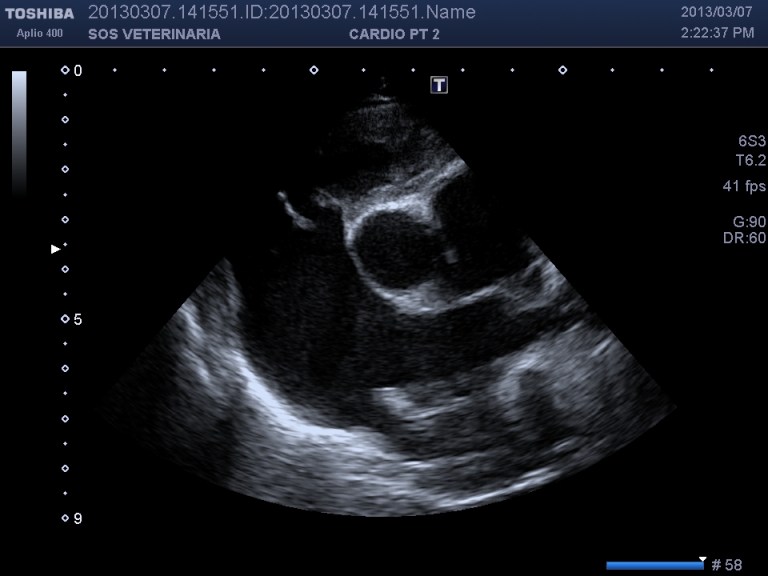

Ecco i filmati piu’ significativi osservare il flusso laminare che scorre parallelo alla parete laterale dell’arteria polmonare non piu’ continuo ma annullato in sistole dalla gittata in polmonare ,nel terzo filmato si vede l’ampolla del dotto